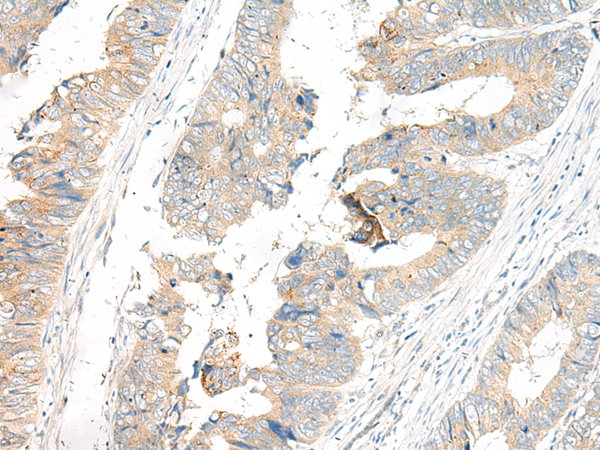

分类: 科研抗体货号: P06574别名: EARS; EPRS; PARS; QARS; QPRS; HLD15; PIG32; GLUPRORS应用: IHC反应种属: Human, Mouse